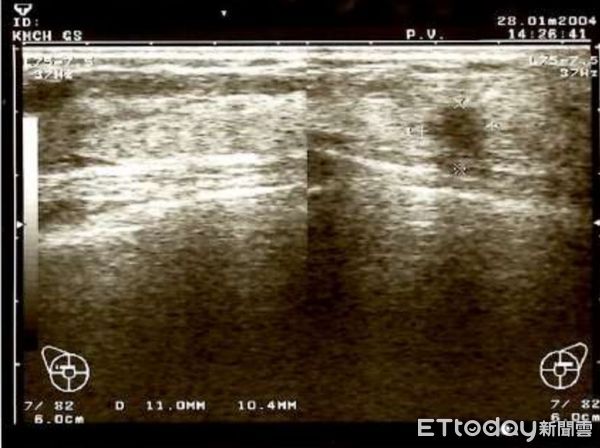

▲▼張女士罹患荷爾蒙陽性乳癌,追蹤長達16年突復發並且骨轉移。(圖/記者許宥孺翻攝)

荷爾蒙陽性乳癌是一場與時間對抗的耐力賽,今年72歲的張女士曾是安養機構照護人員,51歲時檢查確診早期荷爾蒙陽性乳癌,經完整手術與藥物治療後規律追蹤16年,隨著姊妹相繼過世,照顧母親的壓力變大,某天突然感覺「閃到腰」,就醫檢查,發現「骨頭被癌細胞吃掉」,已是乳癌併發骨轉移,目前持續配合治療追蹤,與癌症對抗。